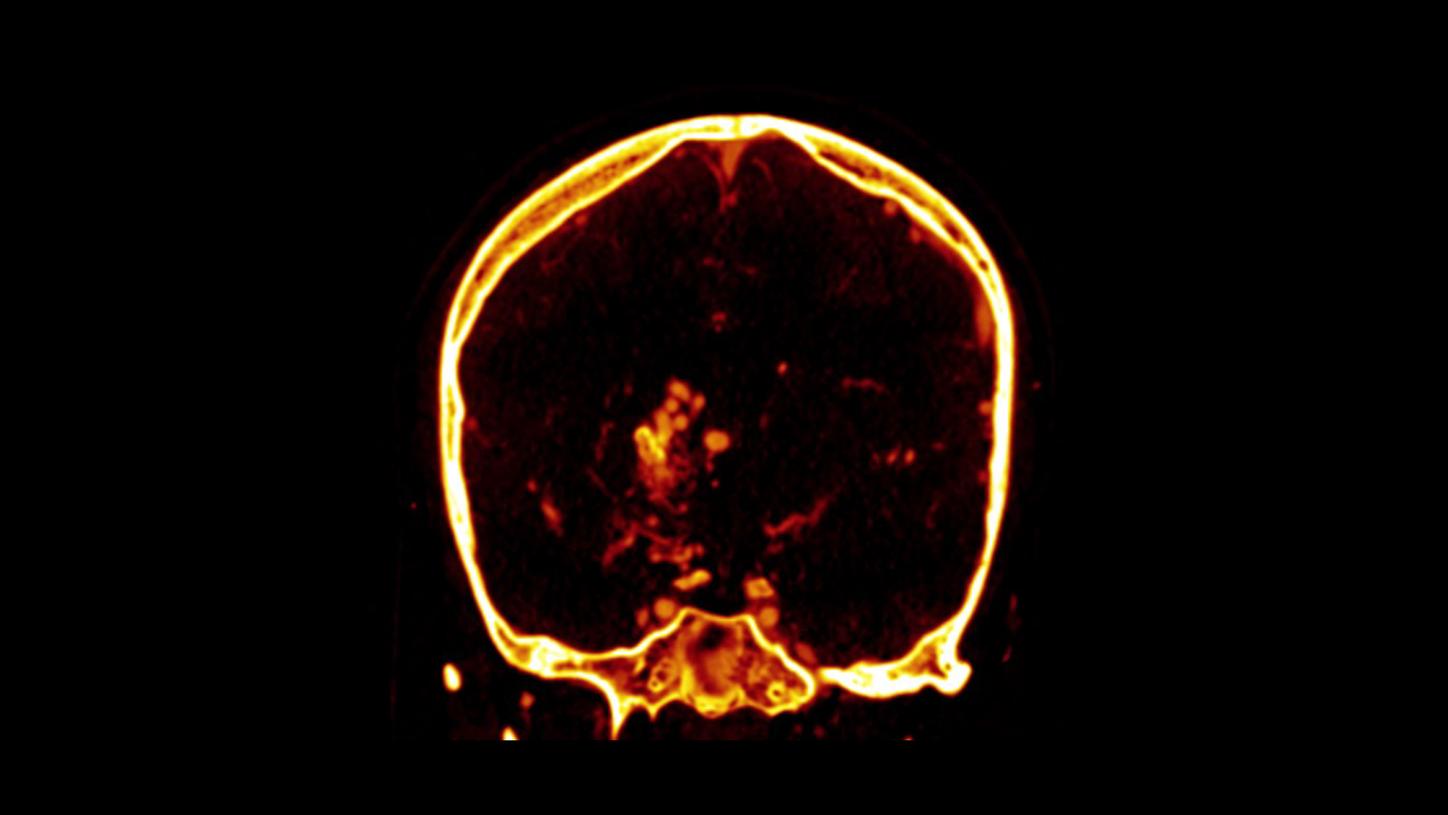

example of hemorrhage visualization